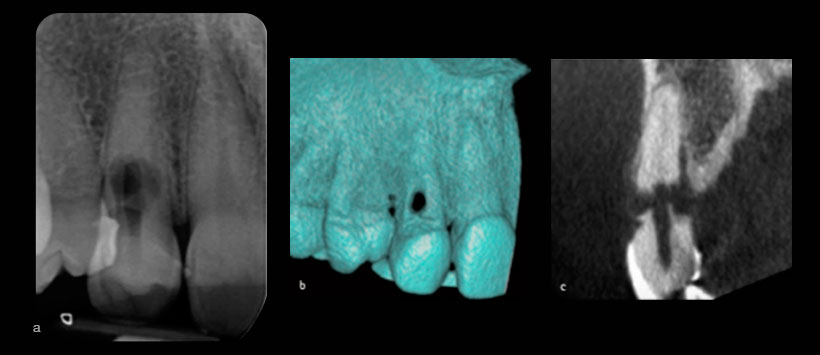

Si se sospecha una reabsorción, se deben tomar una o más radiografías periapicales. Se deben considerar las radiografías adquiridas mediante la técnica paralela, ya que esta técnica proporcionará más información sobre el sitio y el tipo de lesión. Las lesiones internas, sin embargo, deben permanecer en una posición similar en relación con el conducto radicular. Las limitaciones de la radiografía dental de rutina son ampliamente conocidas. Superposición de las características anatómicas, distorsión inadvertida cuando se usan soportes de película y la naturaleza bidimensional de la imagen puede dar como resultado una imagen menos que ideal. (Figura 1) Además, se ha demostrado que las radiografías pueden no ser lo suficientemente sensibles como para permitir el diagnóstico de lesiones de resorción externas. Se ha demostrado que el tamaño de la lesión, su ubicación, su anatomía local y su densidad ósea influyen en la detección de lesiones.

Varios informes de casos han demostrado que la CBCT puede mejorar el diagnóstico de las lesiones. (Figura 2) Estos estudios han sido respaldados por estudios clínicos, aunque la mayoría son in vitro. El uso de CBCT permite la determinación precisa del sitio, tipo y extensión de la lesión. Ha habido un aumento en el número de publicaciones relacionadas con el uso de CBCT para el diagnóstico de lesiones internas y externas, aunque muchos son informes de casos. La mayoría de los estudios clínicos se relacionan con lesiones de raíz generadas artificialmente. No obstante las indicaciones son que el CBCT es valioso en el diagnóstico y, en última instancia, en el manejo de la reabsorción. Como la exposición a la radiación ionizante debe mantenerse al mínimo, la derivación para CBCT solo debe hacerse si será de gran ayuda en el diagnóstico o la gestión.